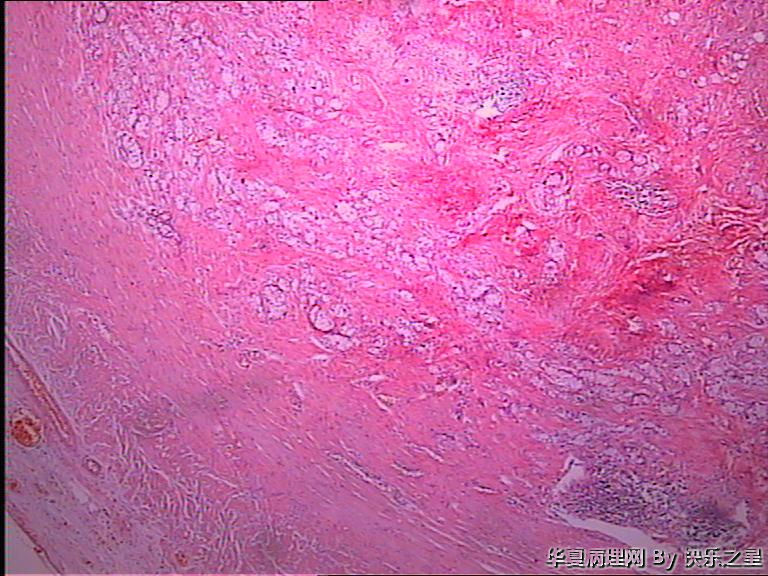

阑尾杯状细胞腺类癌?

• 阑尾杯状细胞腺类癌?图1

图1

男,73岁,因回肠坏死手术,术中切除部分回肠及回盲部,附带 阑尾,长6.5,粗0.7-1.2,表面水中、充血,管腔闭塞,成实性,切面灰白、暗红,质中。

回肠为肠坏死表现,回盲部肠壁充血、水肿,均未见肿物。